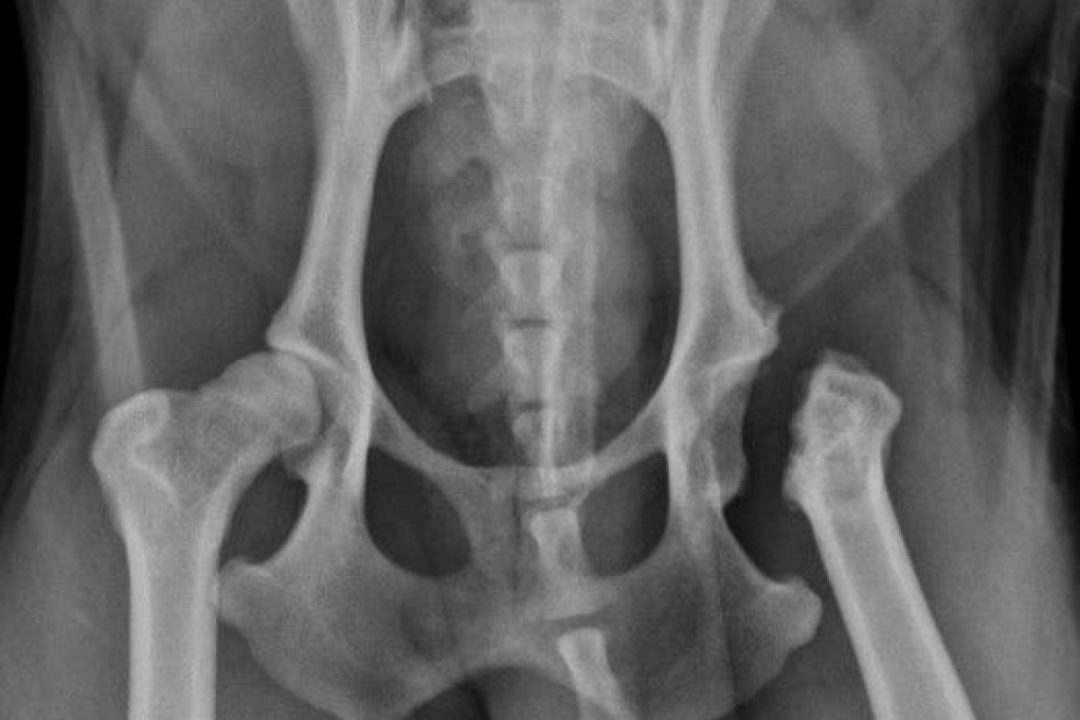

Pip – 1 year female Jack Russell

Acupuncture, Hydrotherapy, Surgical